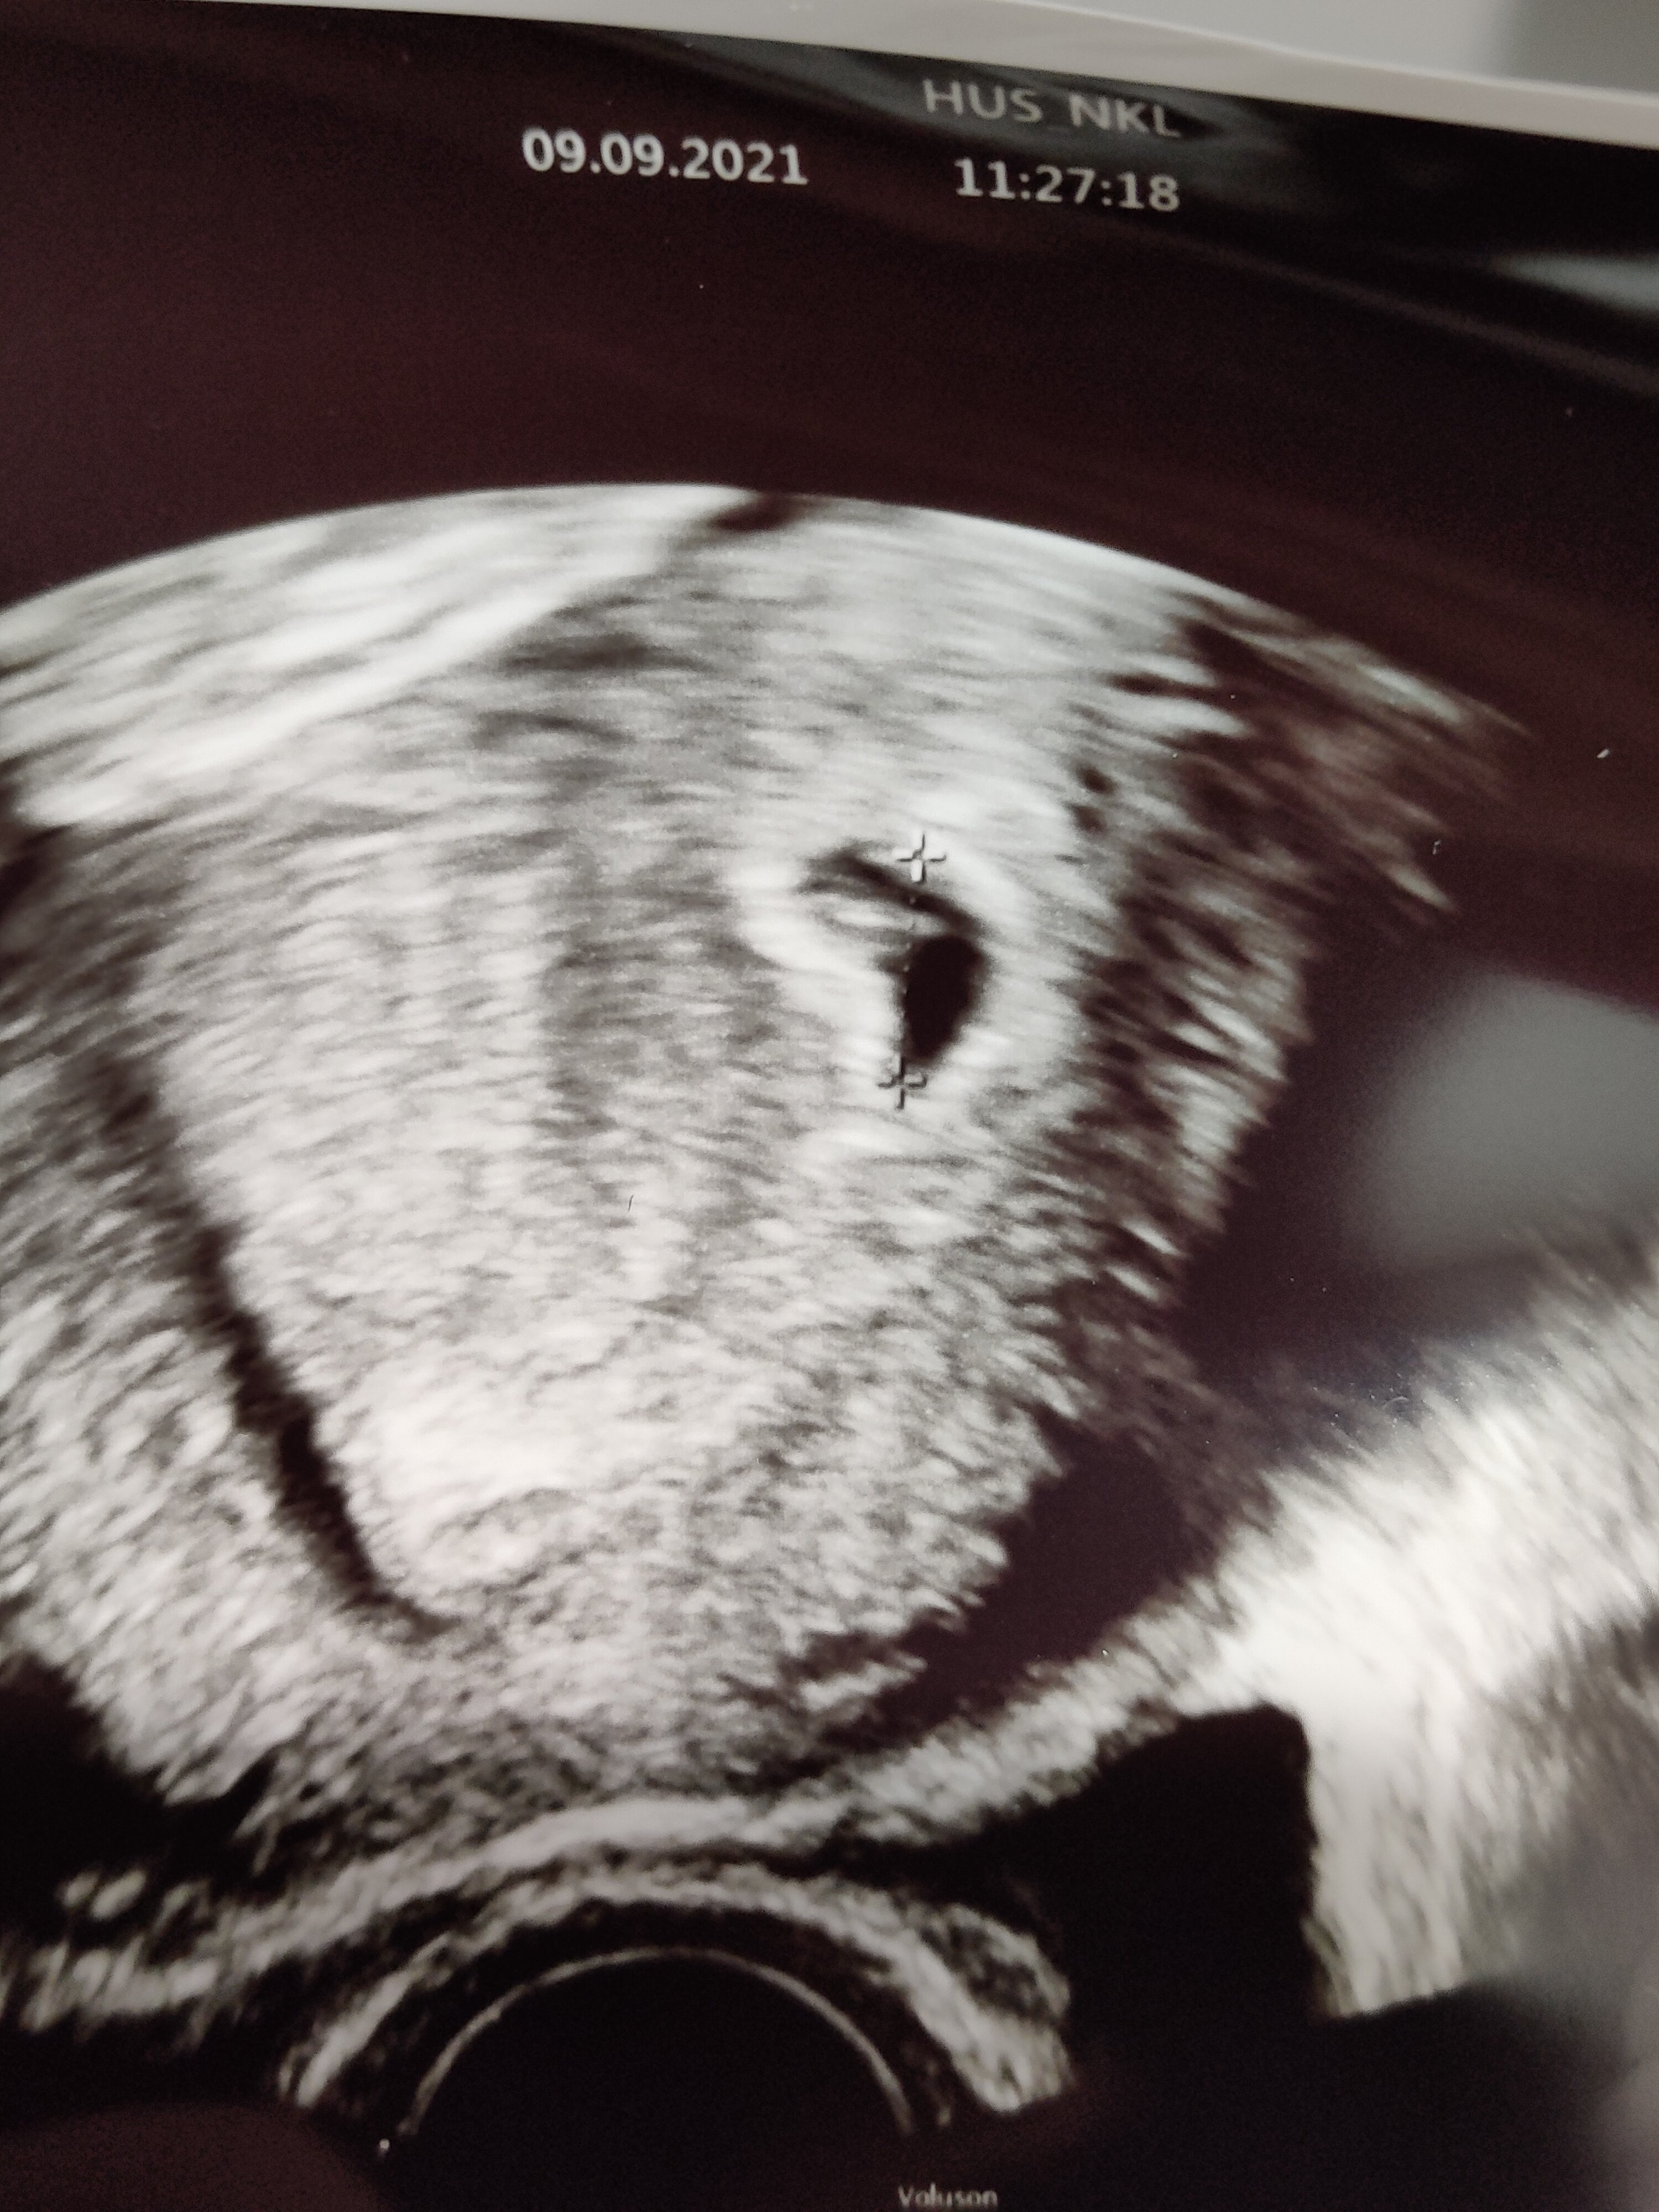

kai se voi vielä tuulimuna olla tai tietty mennä kesken mutta ensin näki vain pussin ja lopussa siellä sisälläkin jotain? Eli jos sisällä näkyy jotain niin ei voi olla tuulimuna? Sykettä ei näkynyt mutta puhui että joku kaiku taitaa näkyä. Onneksi 21.9. uusi ultra